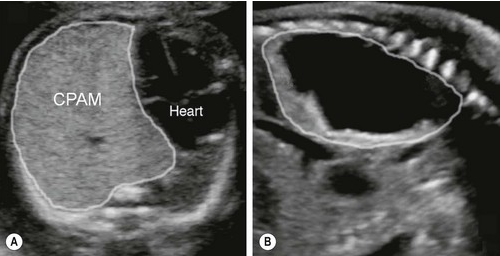

Trên siêu âm thai, bệnh nang tuyến phổi có thể biểu hiện bằng một nang lớn, nhiều nang nhỏ hoặc một khối tăng âm đồng nhất trong lồng ngực.

Bác sĩ sẽ đánh giá vị trí khối, kích thước, mức độ đẩy lệch trung thất và ảnh hưởng đến tim thai. Một yếu tố quan trọng là có hay không dấu hiệu phù thai.

Chỉ số CVR thường được sử dụng để ước tính nguy cơ biến chứng. Khi khối lớn nhanh hoặc CVR tăng cao, nguy cơ phù thai sẽ tăng theo.

Dựa trên đặc điểm mô học, bệnh được chia thành nhiều type. Trong thực hành siêu âm thai, thường mô tả theo ba dạng chính.

Type 1 có một hoặc vài nang lớn, thường trên 2 cm.

Type 2 gồm nhiều nang nhỏ, dưới 2 cm.

Type 3 là khối tăng âm đặc, gần như không thấy cấu trúc nang rõ ràng.

Phân loại giúp mô tả chính xác hình ảnh. Tuy nhiên, tiên lượng phụ thuộc nhiều hơn vào kích thước khối và diễn tiến theo thời gian.